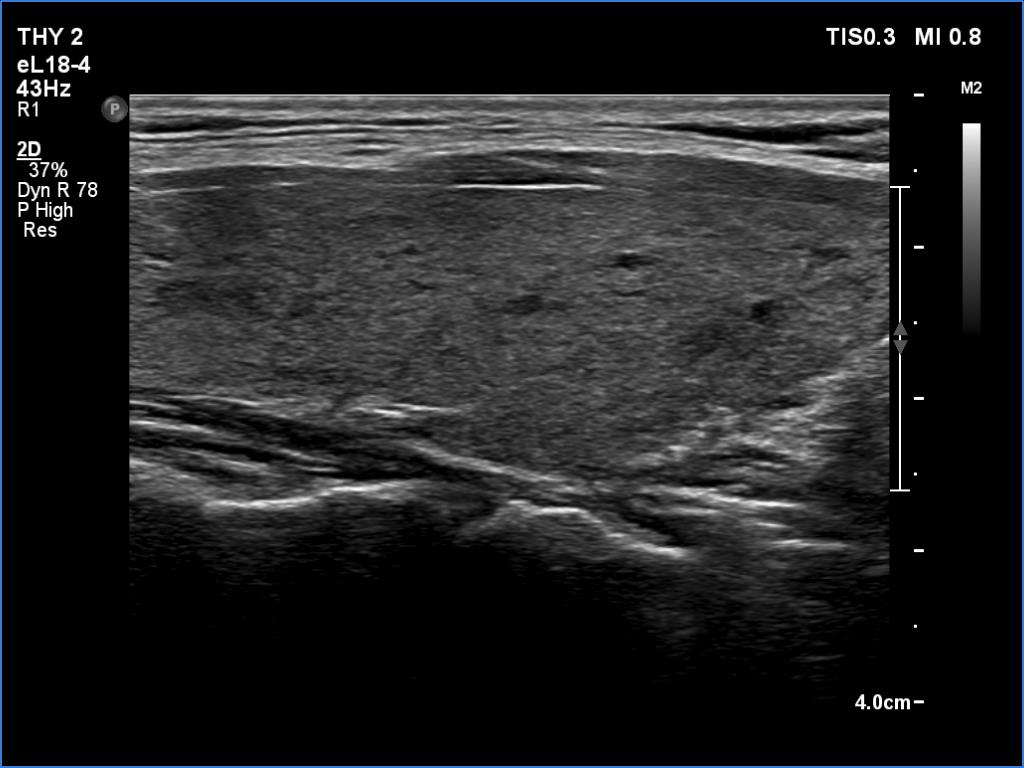

Right lobe, longitudinal scan

Left lobe, longitudinal scan